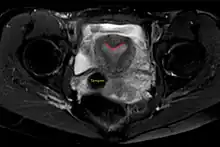

Arcuate uterus (marked in red) seen on MRI | |

The arcuate uterus is a form of a uterine anomaly or variation where the uterine cavity displays a concave contour towards the fundus. Normally the uterine cavity is straight or convex towards the fundus on anterior-posterior imaging, but in the arcuate uterus the myometrium of the fundus dips into the cavity and may form a small septation. The distinction between an arcuate uterus and a septate uterus is not standardized.